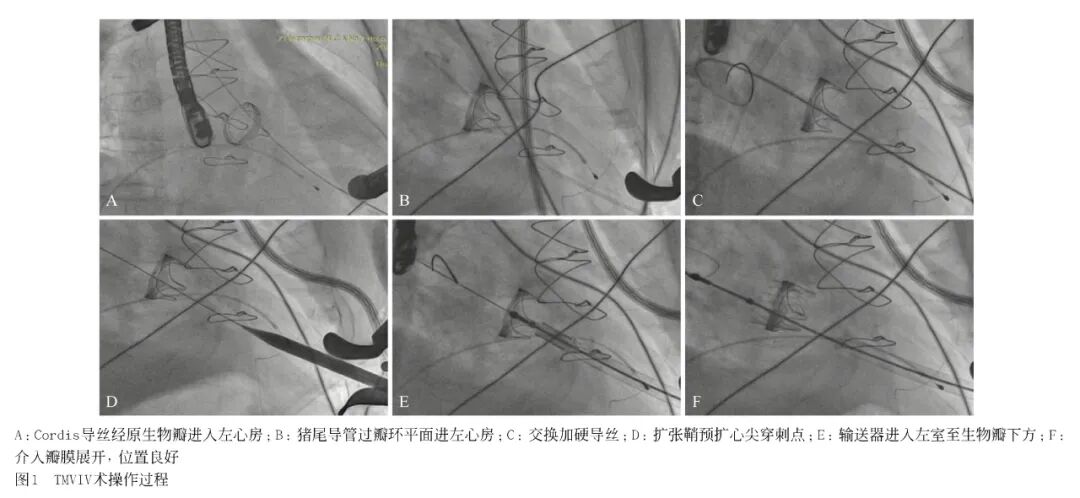

TEE显示J-Valve瓣架位置良好,瓣叶开放活动度正常,左房内压力为16 mmHg,较术前(44 mmHg)明显下降;TEE示舒张期前向流通畅,峰值流速及平均压差较术前明显降低,未见瓣周漏,见图2;次日复查TTE:MPG=4 mmHg(术前10 mmHg),患者临床症状缓解,复查胸片较术前改善。